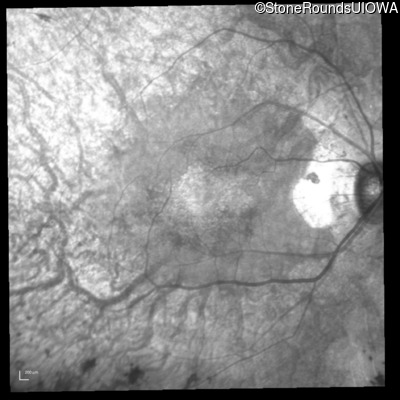

Infrared Fundus Photograph - Right - 20/20

Exemplar